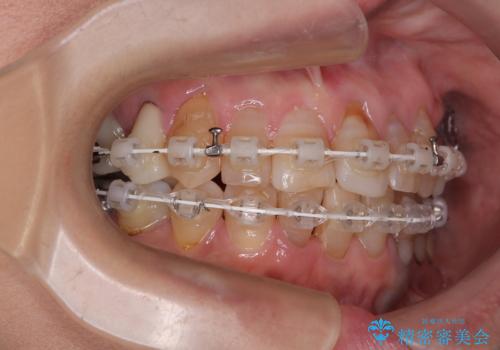

- 矯正装置

- 審美装置

- 治療期間

- 2年1ヶ月

- 治療回数

- 30回以上